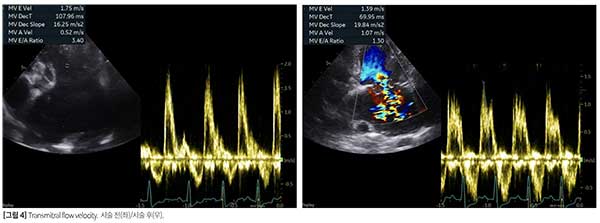

좌심방 감압술은 [증례 1]과 동일한 방식으로 진행됐다. 시술 후 10일 차 재검에서 좌심방 압력 상승 관련 지표는 여전히 좋지 않았지만(E peak 1.75->1.39m/s, E/Em 20.19->18.92, E/IVRT 5.42->2.14) 시술 전과 비교 시 개선된 양상을 보였다[그림 4].

좌심 리모델링이 뚜렷했고(LA/Ao 3.3, LVIDDn 2.12), E peak 1.75m/s, E/Em 20.19, E/IVRT 5.42로 좌심방 압력은 상승됐으며, 좌심의 수축 기능 장애도 동반돼 있었다. 수축기 폐동맥압은 52mmHg로 폐고혈압이 경-중등도로 평가되었으나 관련 임상 증상은 없었다.